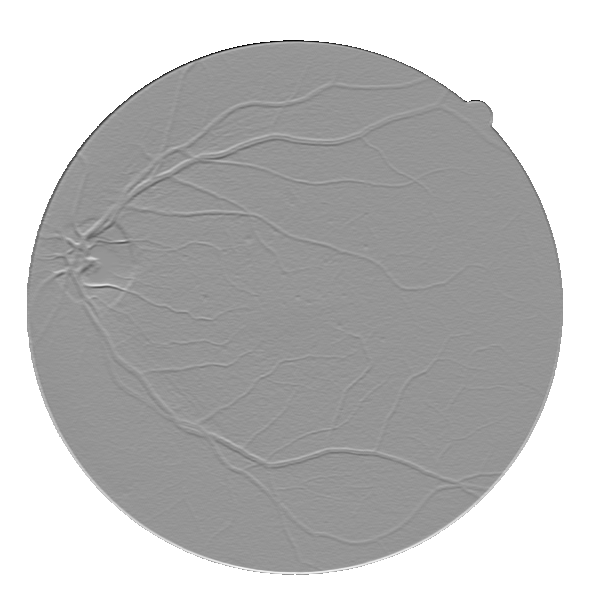

We started by evaluating our Base System regarding data augmentation, prediction and regularization. The results of each variant are shown in Table 3, while the probabilistic predictions can be seen in Fig. 4. All tests were performed under the same conditions, with the only source of variability being the component under study.

Considering the Base System as the reference, we can see that reducing the number of patches by four strongly deteriorated the results in terms of Acc and AUC. Besides this, either when using original or elastic patches to keep the initial number of samples, the differences to the reference remained almost the same. Looking directly at Fig. 4, we notice that these approaches favored the simultaneous appearance of FN and FP, with elastic patches leading to greater tortuosity in the detected vessel segments. Overall, this hints that the network benefited the most from the information encoded by the rotations. Another important note is related to the way those rotations were presented to the network. Recalling section 2.4, we have seen that some data augmentation strategies designed for FC-CNNs (Dieleman et al.,, 2016; Worrall et al.,, 2016) require the rotated versions to be arranged consecutively. The Consecutive Rotations test hints that a deterministic proximity between the rotated patches is detrimental to the performance of the FCN, with the network showing more difficulties in detecting vessel segments as can be seen in Fig. 4.